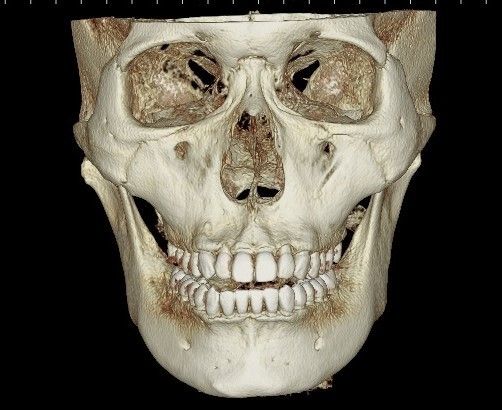

2. 입다물때 비대칭 별로 티안나는것 같은데 입벌리고 아랫치아보면 치아가 한쪽으로 기운느낌이 드는데

턱관절문제 일까요? 치아가 기운 문제일까요? 양쪽 턱뼈 길이차이 문제일까요?

2. 현재로서는 골격적 비대칭일 가능성이 더 큽니다. 즉 교정을 이용해서 이를 해결하기는 쉽지 않으며 보통 골격이 틀어진 경우 교정을 하더라도 한계가 있습니다.